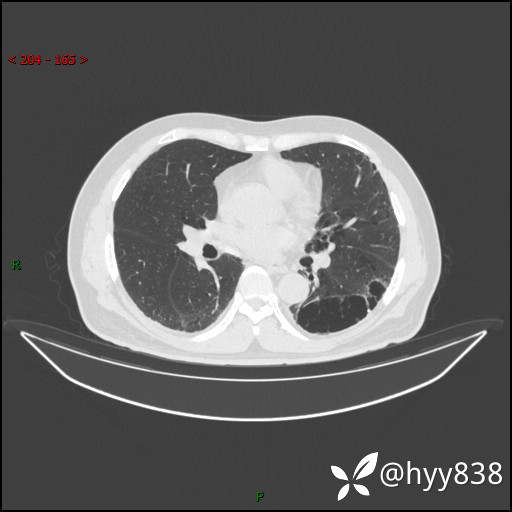

一周后胸部CT